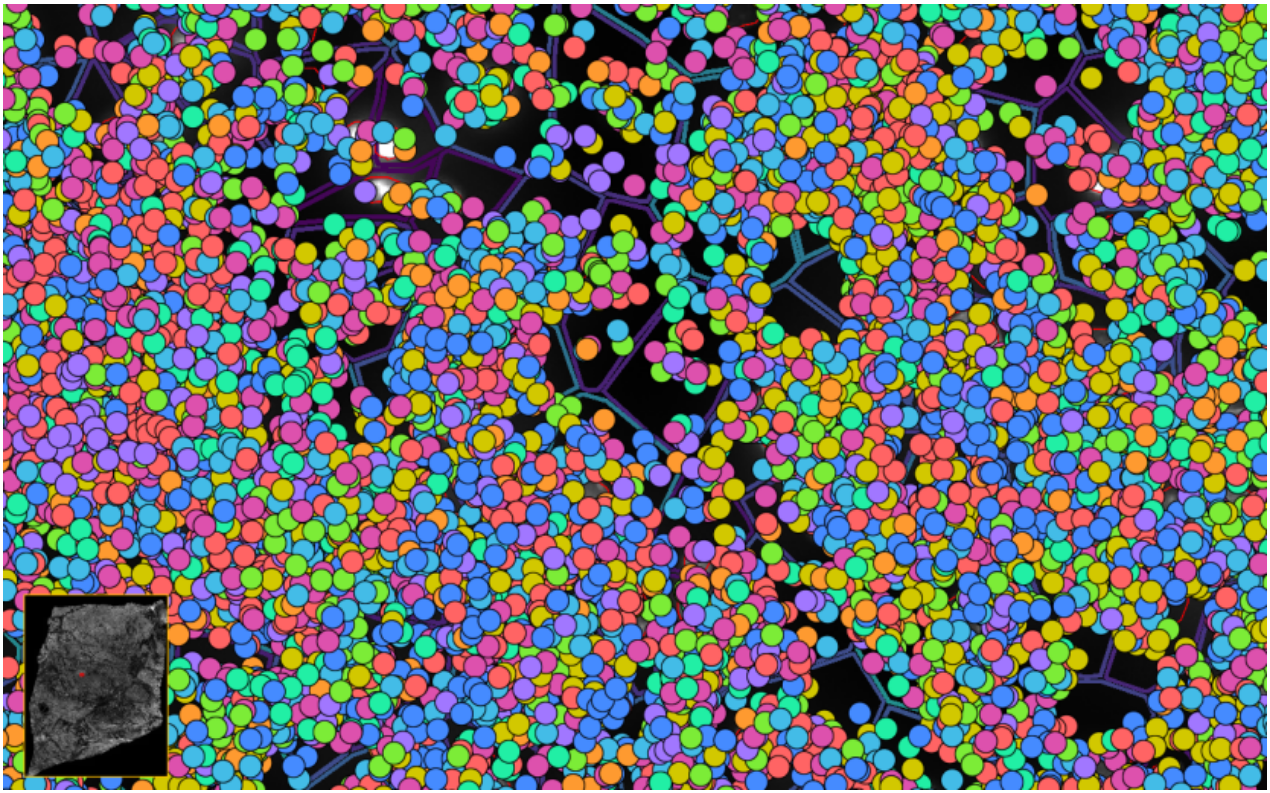

image.png

ͼ2£ºXeniumÊý¾Ý¸ÅÀÀ